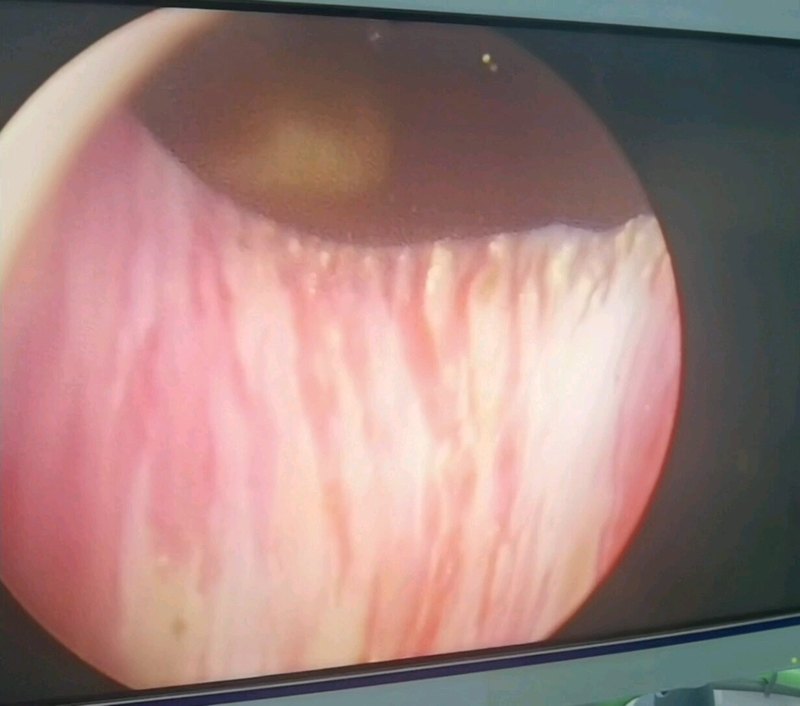

- 患者:女 50岁最后交流时间 02.07现在医生在吗总交流次数7已给处置建议

- 乳腺增生 第一张是我单位体检的报告,后一张是今天做钼靶的报告,姚医生帮... 后期需要我做什么,严不严重,需不需要干预总交流次数9已给处置建议

- 甲状腺结节 甲状腺术后五年每天吃1.5粒药,是否需要改变药量 这是7... 我是术后五年,现在药量是每天1.5粒,请问这个药量需要变吗?总交流次数7已给处置建议

- 甲状腺乳头状癌术后 甲状腺癌术后复查,请姚医生帮看一下用药是否需调整,现每天用量... 复查结果是否正常?总交流次数3已给处置建议

- 21年甲状腺癌半切 第一张是22年11月早上空腹未吃优甲乐测的,第二张是今天早晨... 需要调药,还是如何处理总交流次数12已给处置建议